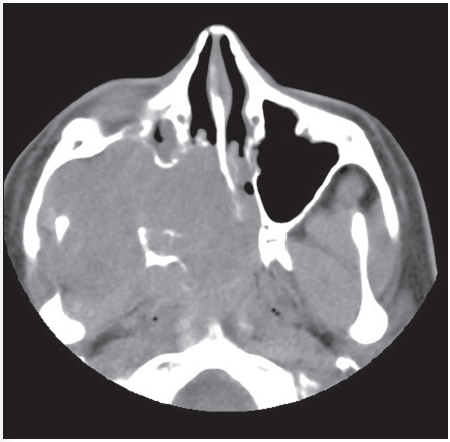

A Middle Aged Male With Progressing Blurry Vision Consultant360